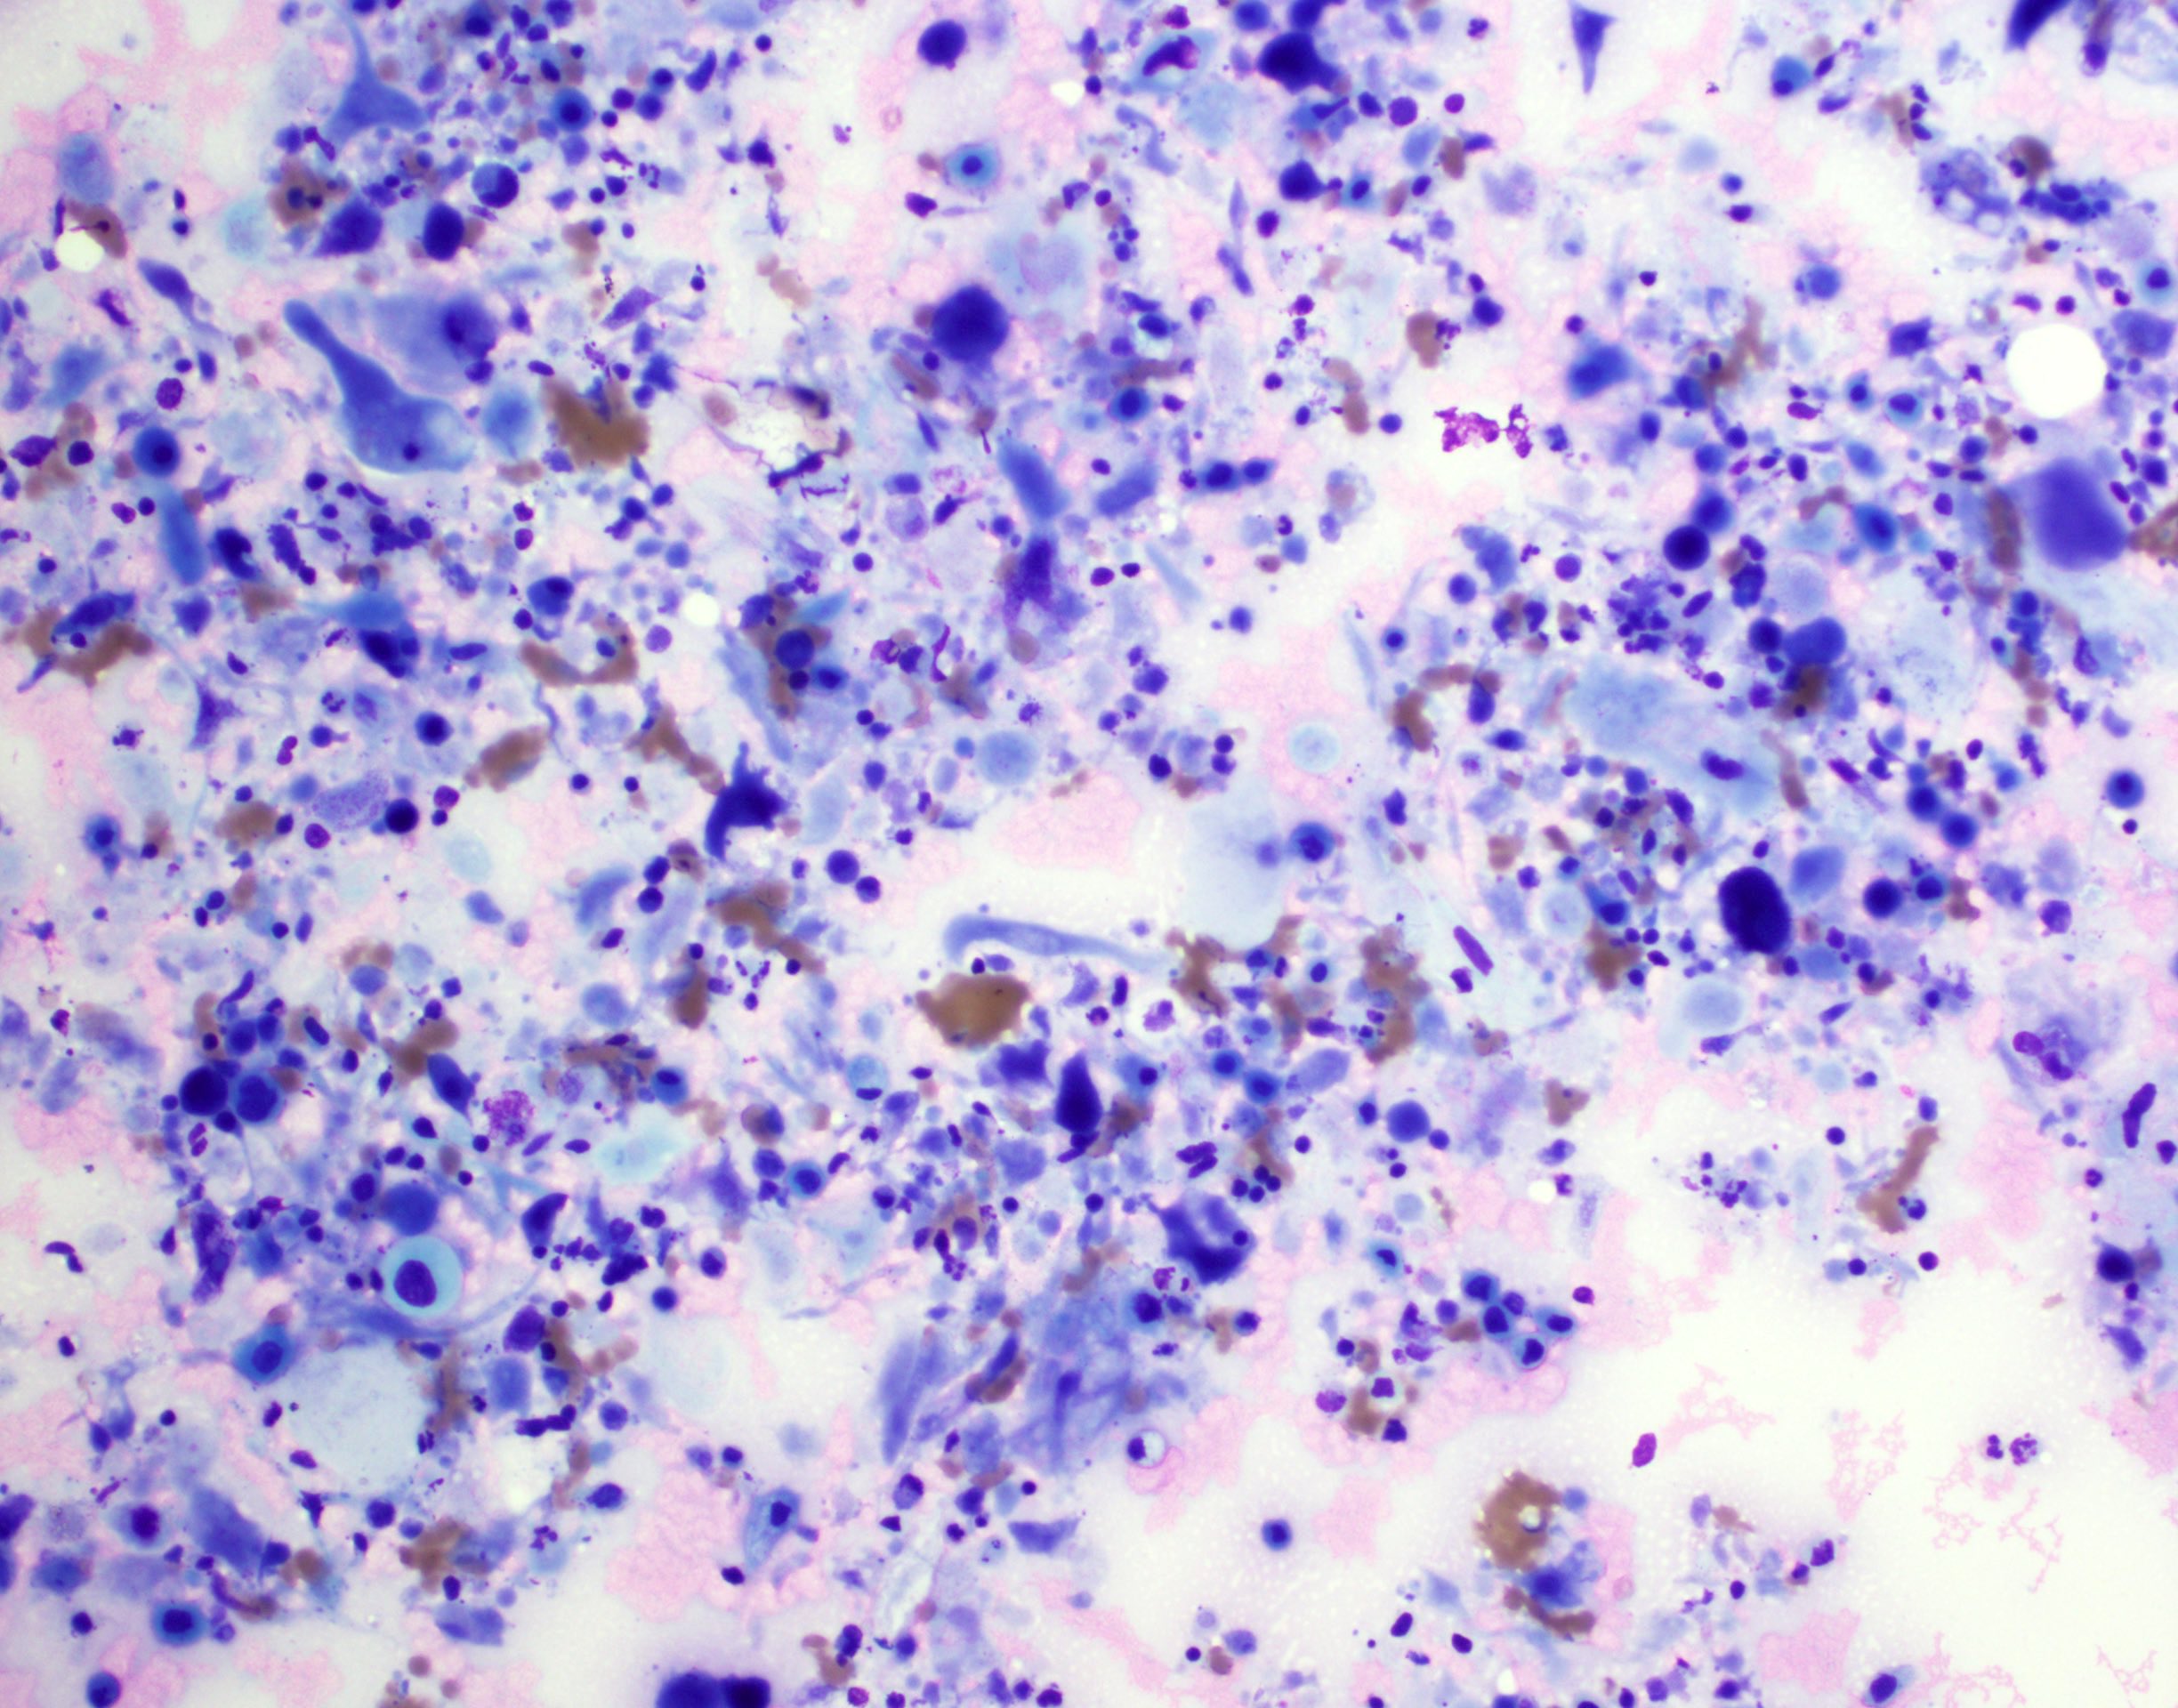

Cytology description

- Role of cytology only in investigation of regional or distant metastases

- Appearance depends on type and differentiation

- Conventional squamous cell carcinoma shows sheets and small clusters of large polygonal malignant cells with intercellular bridges and cytoplasmic or extracellular eosinophilic keratin

Cytology images